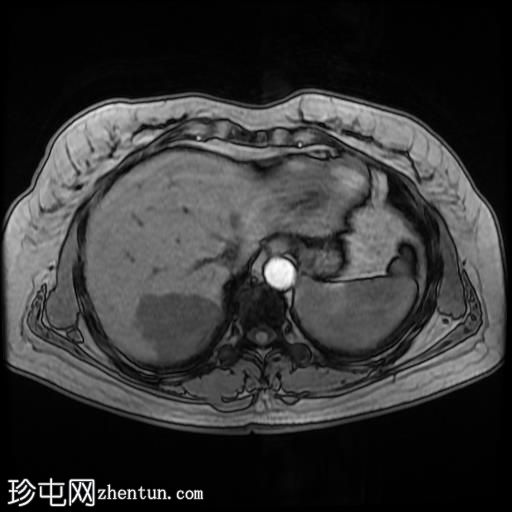

轴位T1加权像

GE IPOP序列

1.jpg

肝脏第7段可见一边界清晰的分叶状肿块。T1加权像呈低信号,T2/T2脂肪抑制序列呈高信号,动脉期呈不连续结节状周边强化,门静脉期呈向心性强化,延迟期完全强化。DWI序列呈高信号,ADC值呈混合信号。